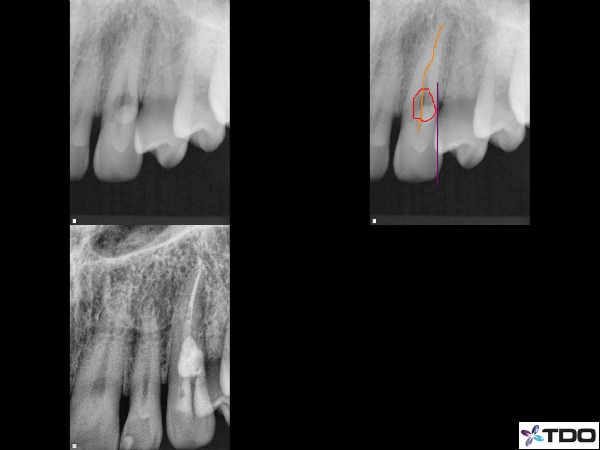

–external root resorptive defects (figure 6)

Fig.6 This tooth was referred for evaluation with a moderate degree External Cervical Invasive Resorption process on the buccal surface. There was initially a 9mm buccal probing with associated buccal bone loss. I performed RCT and then surgically entered the site to repair the defect with Geristore. At our 1 month check-up the sulcus depth was restored back to 4mm.

–horizontal root fractures (depending on location tooth may or may not be saved) (figure 7)

Fig.7 This lateral root lesion appears near the crestal bone level on the mesial side of tooth #9. The illustrations in orange and red show the lesion and a horizontal root fracture.